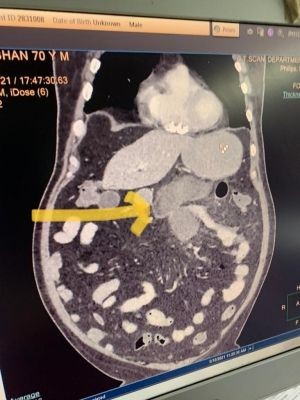

"The CT scan revealed Kumar's small intestine (jejunum) had been perforated. His Covid disease also had worsened by now requiring ventilator support. The patient was admitted and taken up urgently for surgery."

According to Dr Dhir, "Ulceration of Jejunam (first part of small intestine) in the patient raised my suspicion of fungal disease and patient was immediately started on anti-fungal treatment. We sent the portion of removed intestine for biopsy."

"The CT scan revealed small intestinal perforation similar to the first patient," the hospital authorities said.